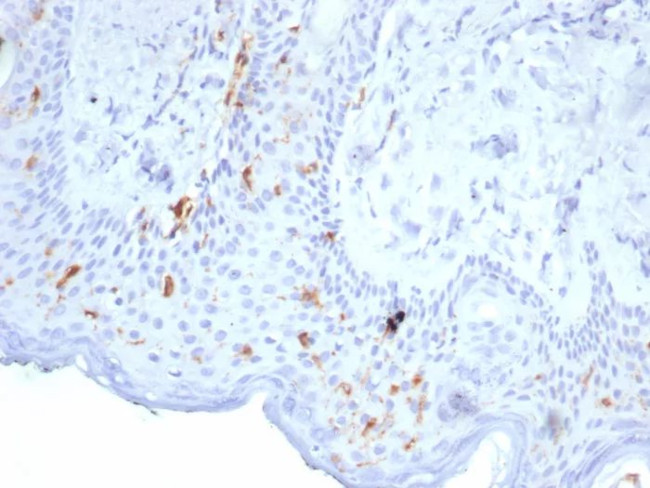

Langerin/CD207 (Marker of Langerhans Cells) Antibody in Immunohistochemistry (Paraffin) (IHC (P))

Langerin/CD207 (Marker of Langerhans Cells) Antibody (50489-MSM6-P1ABX) in IHC (P)

Formalin-fixed, paraffin-embedded human skin stained with Langerin Mouse Monoclonal Antibody (LGRN/7356). HIER: Tris/EDTA, pH9.0, 45 min. 2°C: HRP-polymer, 30 min. DAB, 5 min. {{ $ctrl.currentElement.advancedVerification.fullName }} 验证信息 View more

Positive Control:Human skin.

Cellular Location: Cell Surface. Cytoplasm.

Langerin (CD207) is a type II membrane-associated C-type lectin known to be expressed exclusively by Langerhans cells. Lamgerin recognizes mannose residues via its single carbohydrate recognition domain (CRD). Langerin is localized not only on the cell surface, but also intracellularly in close association with Birbeck granules. Transfection of Langerin cDNA into fibroblasts creates a compact network of membrane structures with typical features of Birbeck granules (BG). Langerin is thus a potent inducer of membrane superimposition and zippering leading to BG formation.